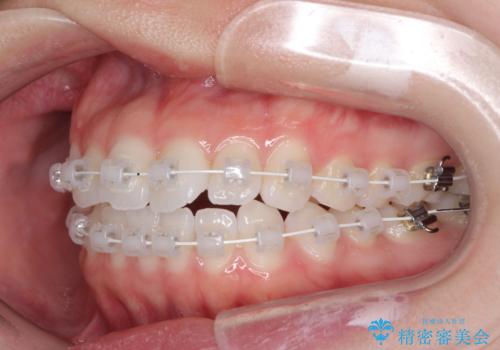

- 矯正装置

- 審美装置

- 海外留学を前に上下のデコボコと奥歯の咬み合わせを改善したいとのことで来院された患者様です。

期間が限られていたため、ワイヤー装置による矯正治療を行うこととしました。

治療開始から4ヶ月ほどで概ね歯列が整い、その後の3ヶ月で細かい部分を仕上げていきました。

短期間で綺麗に仕上がり、患者様には大変満足していただきました。